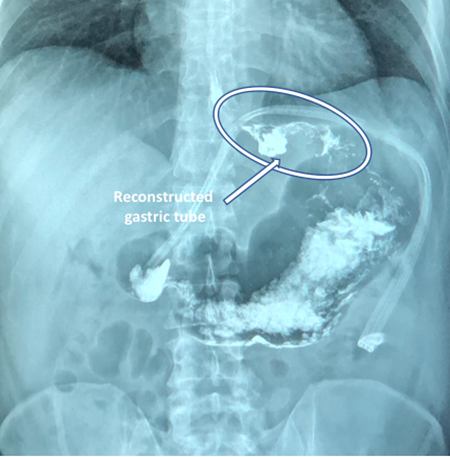

The ultrasound showed a large solid abdominal mass in the upper abdomen. The computed tomography reported a solid tumor with dimensions of 223.1mm X 142.9mm with peripheral vascularity, central necrotic areas, and displacement of splenic artery and biliary sludge. (Figure 1) The endoscopy revealed an ulcerated tumor that extended from the cardia to the posterior part of the upper third of the body of the stomach. The biopsy confirmed gastrointestinal stromal tumor (GIST). Therefore, informed consent was obtained for the surgical procedure and he was scheduled for tumor resection and cholecystectomy.

The esophago-gastroduodenal series taken a week after surgery (Figure 4) showed acceptable reconstruction of the stomach, without leaks, and adequate passage of contrast media.

Figure 4 Esophago-gastroduodenal series taken a week after surgery with acceptable gastric reconstruction forming an upper gastric tube.